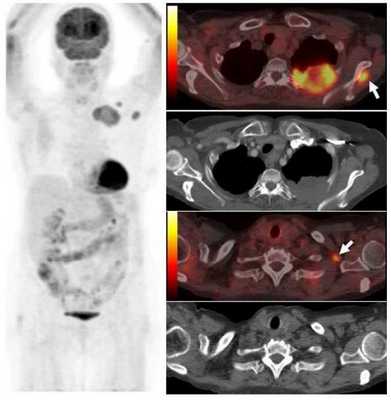

В первичном обследовании пациента, страдающего раком легкого, должны принимать участие несколько специалистов: опытный рентгенолог, специалист по ядерной медицине (радионуклидным методам — сцинтиграфии и ПЭТ), рентгенохирург (специалист в области интервенционной радиологии), пульмонолог, торакальный хирург; необходимо также использовать точные и экономически эффективные методы диагностики. Существующие на данный момент руководства содержат рекомендации, что методы нужно выполнять любому пациенту, у которого имеется высокий риск рака, предпочтительно с выполнением гистологического исследования и взятием образцов ткани. Это позволяет не только установить точный гистологический вариант опухоли, но и правильно стадировать заболевание. Во многих случаях предпочтительнее выполнить биопсию подозрительных лимфоузлов средостения, а не первичной опухоли, что позволяет лучше оценить стадию (например, при биопсии лимофузла с выполнением ПЭТ ставится стадия T2N2, в то время как без ее использования - T2Nx). Кроме того, для опухолей, осложненных обструктивной пневмонией, и образований с выраженными некротическими изменениями, данные играют важную роль для определения области биопсии.

Опухоль левого легкого с частичным некрозом и деструкцией ребер. Визуализируются два метастаза в подключичных лимфоузлах и в мышцах (стрелки), которые на КТ не видны. Необходимо выполнить трансторакальную биопсию той части опухоли, которая расположена в периферических отделах, чтобы получить образец жизнеспособных тканей.